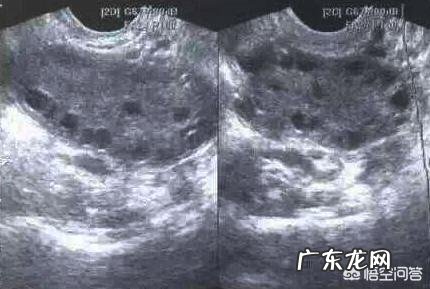

对于多囊备孕生孩子 , 对于有此类情况的粉丝来说就像“迷”一样 。有些人随便戴套都能怀上 , 而多囊粉丝们每天盯着卵泡瞅着排卵期都怀不上 。黄医生提醒各位 , 多囊粉丝备孕做得好孩子同样跑不了 , 不要太着急 。